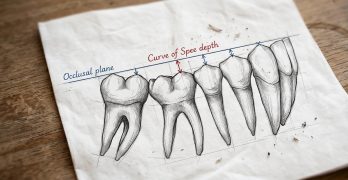

BDR CCCVIII: Curva de Spee y el Ortodoncista

Para cerrar nuesta semana y directo de nuestro infame Baúl del Recuerdo traemos una nota llamada La curva de Spee y el … [Leer más...] acerca de BDR CCCVIII: Curva de Spee y el Ortodoncista